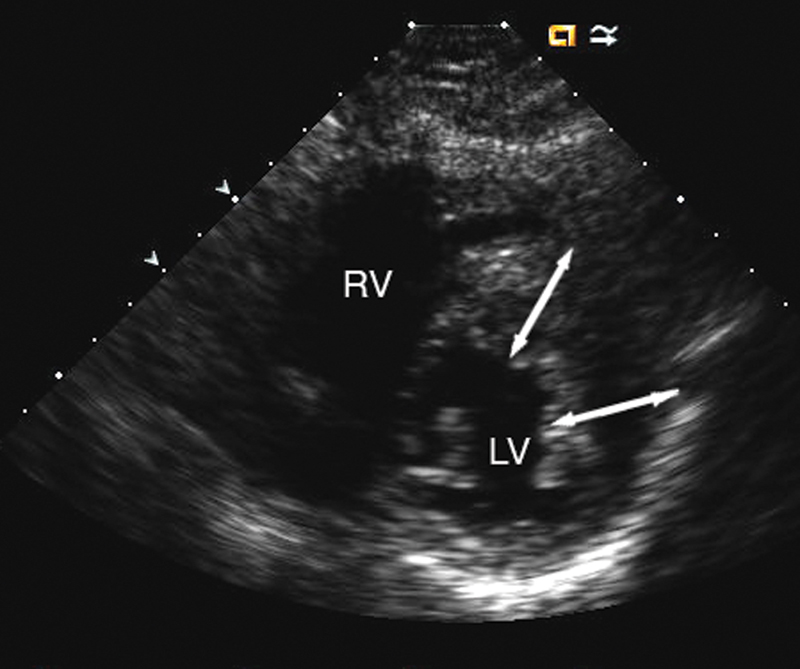

فحوصات تشخيصية لبعض امراض القلب والشرايين التاجية